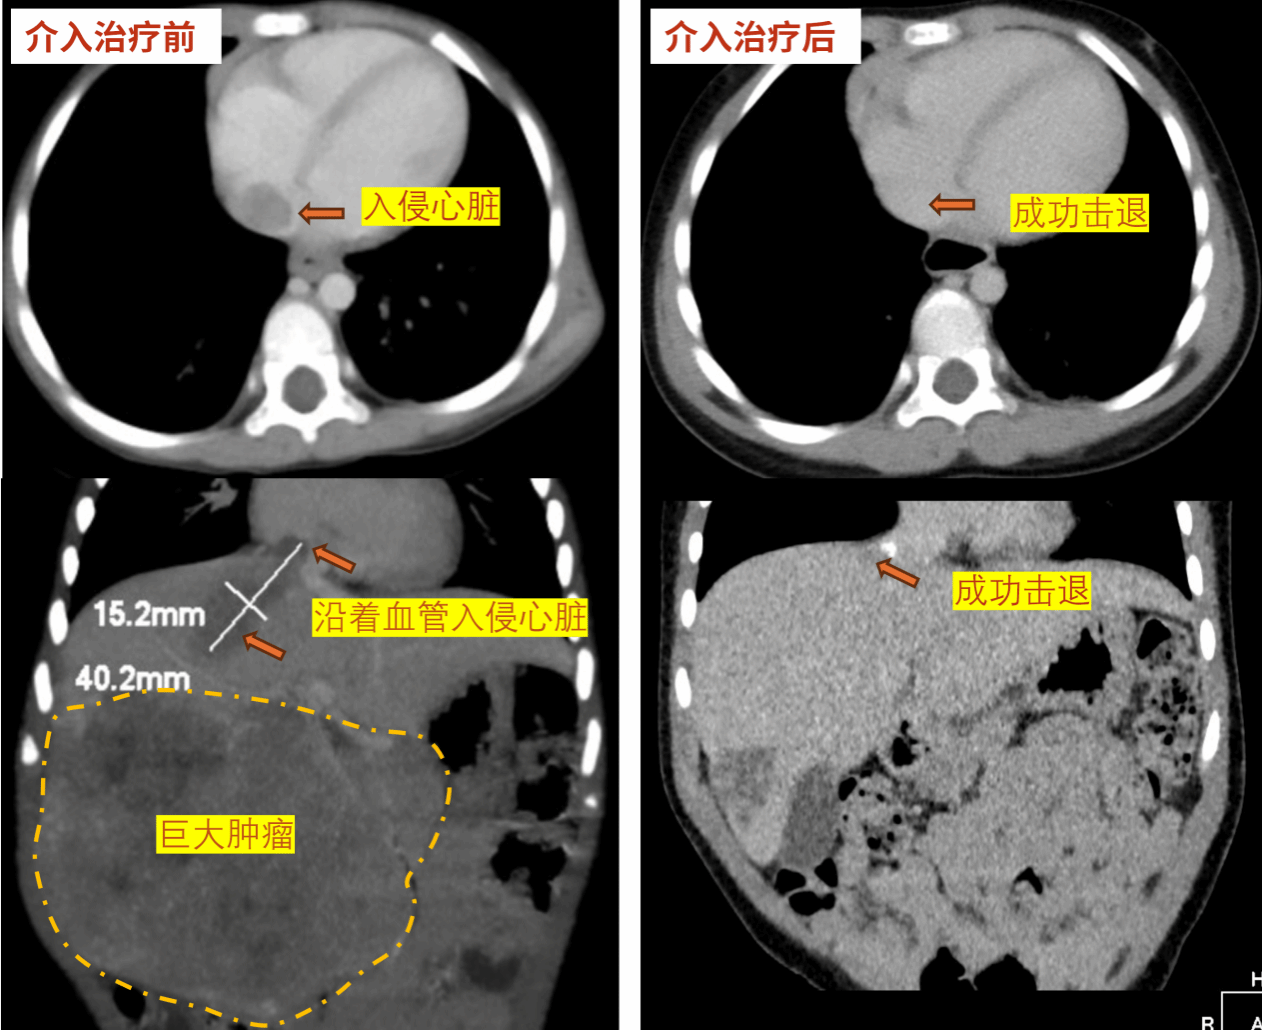

医生们的目光锁定在电脑屏幕上的影像图,图像中显示着一个巨大的阴影:直径约10cm的肝母细胞瘤,不仅盘踞在两岁患儿小宇(化名)脆弱的肝脏上,其“触角”已沿着血管悄然侵入生命的中枢——心脏。

“经过三个标准周期的化疗,虽然肝脏部分的肿瘤有所缩小,但盘踞在心脏血管内的瘤体却顽固不退,达不到理想的手术条件。”熊强副主任医师说,“直接开胸切心风险高、创伤大。”

疗效令人振奋!仅经过一次HAIC治疗,复查影像清晰地显示:原本顽固盘踞在心脏血管内的肿瘤显著缩小,完全退回到肝脏内!

“肿瘤成功退回肝脏,这是一个巨大的转折点!”团队专家难掩激动,“这意味着我们可以避开心脏这个手术‘雷区’,只需针对肝脏实施手术,手术风险和复杂度直线下降,患儿的安全得到极大保障!”HAIC技术成功为根治性手术扫清最大障碍。